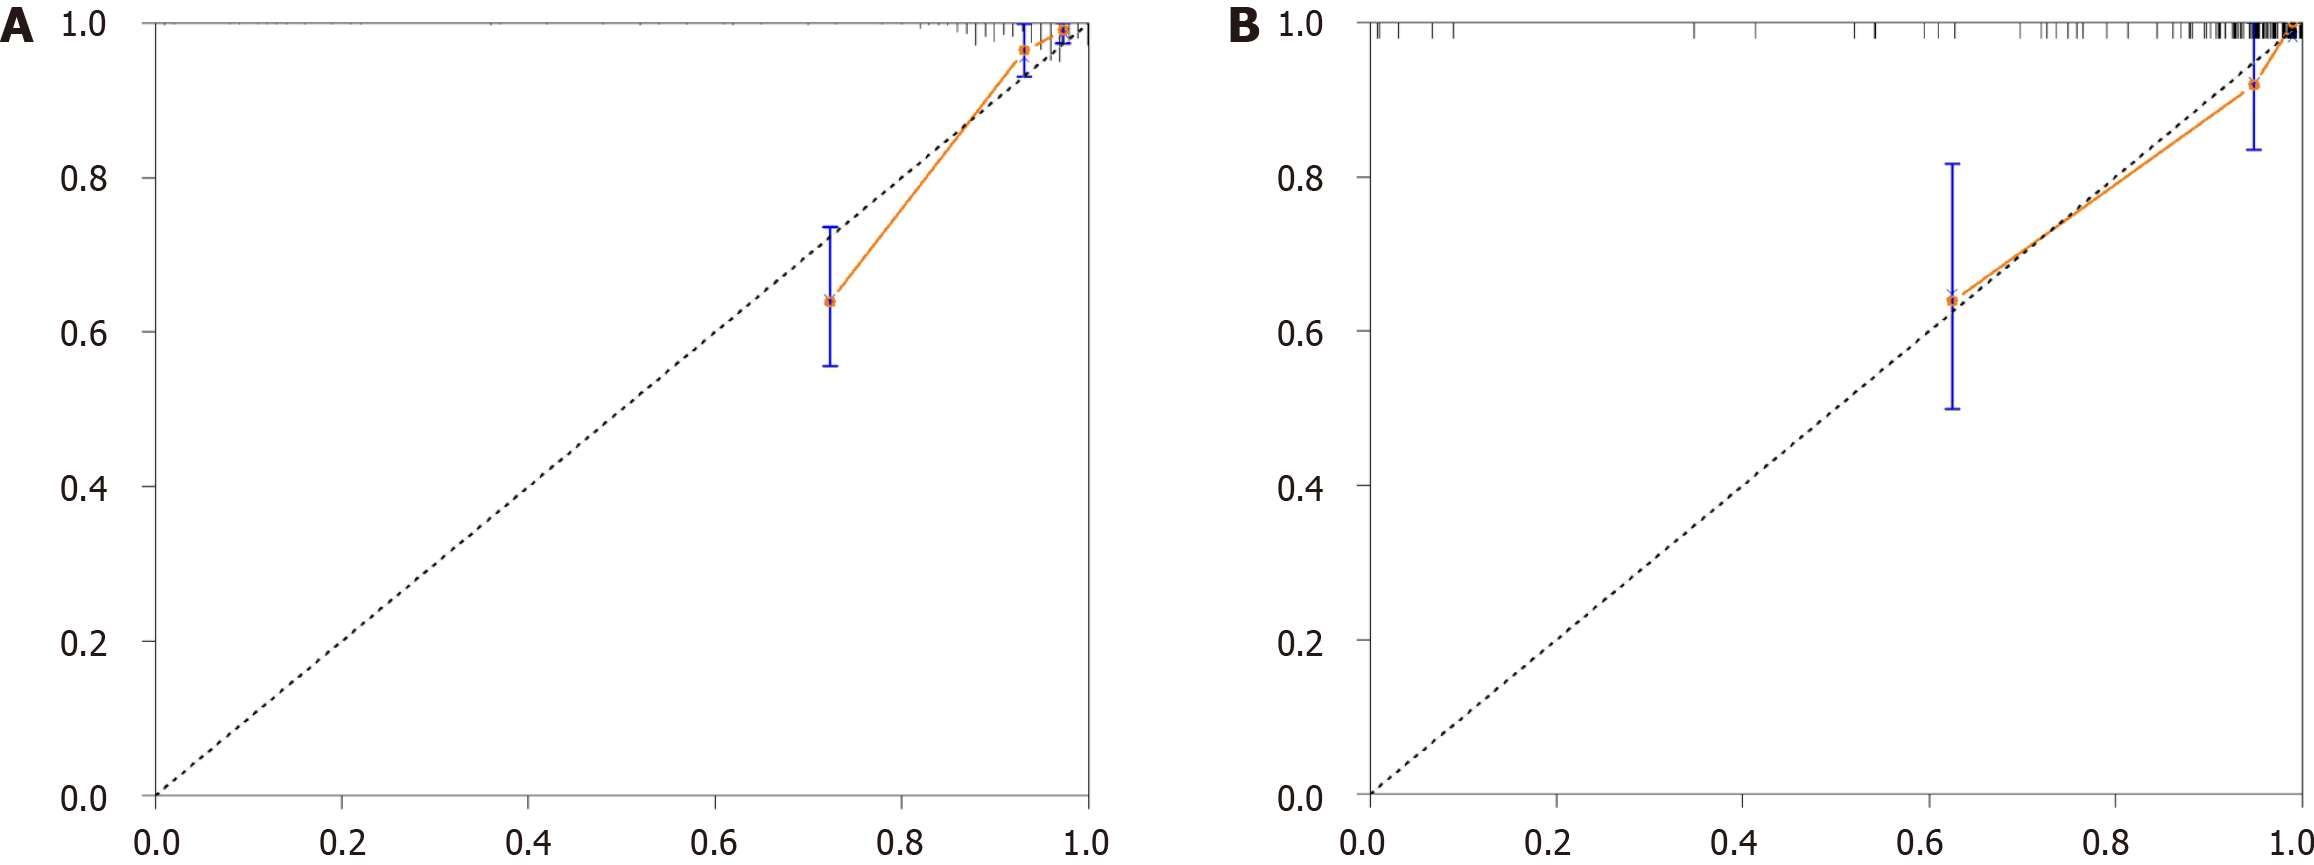

To construct a comprehensive risk prediction model, the radiomics-based Radscore was integrated with significant clinical variables identified through multivariate Cox regression analysis. The final model revealed that the following were independent risk factors for bleeding in patients with BCS. Invasive treatment to relieve hepatic venous outflow obstruction [hazard ratio (HR) = 0.089, 95%CI = 0.044-0.181, P < 0.001), use of anticoagulants (HR = 10.653, 95%CI = 3.102-36.582, P < 0.001), gender (HR = 2.332, 95%CI = 1.057-5.144, P = 0.036), platelet count (HR = 0.992, 95%CI = 0.984-0.999, P = 0.035), and Radscore (HR = 1.545, 95%CI = 1.236-1.932, P < 0.001). These variables were incorporated into a nomogram for individualized prediction (Figure 4). The predictive accuracy of the radiomics + clinical (R + C) model was assessed using the C-index, which achieved values of 0.906 in the training set and 0.859 in the validation set, indicating excellent discrimination. The R + C model demonstrated better predictive performance compared to the clinical-only model (C model) and the radiomics-only model (Radscore; Table 4). ROC curves were generated to assess model discrimination over a 3-year follow-up period. The results showed that the R + C model achieved superior discrimination compared to the individual Radscore and C model, as reflected by its larger AUC in both the training and validation datasets (Figure 5). Calibration curves confirmed a strong alignment between predicted and observed outcomes (Figure 6), while DCA demonstrated the superior net clinical benefit of the R + C model across a wide range of threshold probabilities (Figure 7).